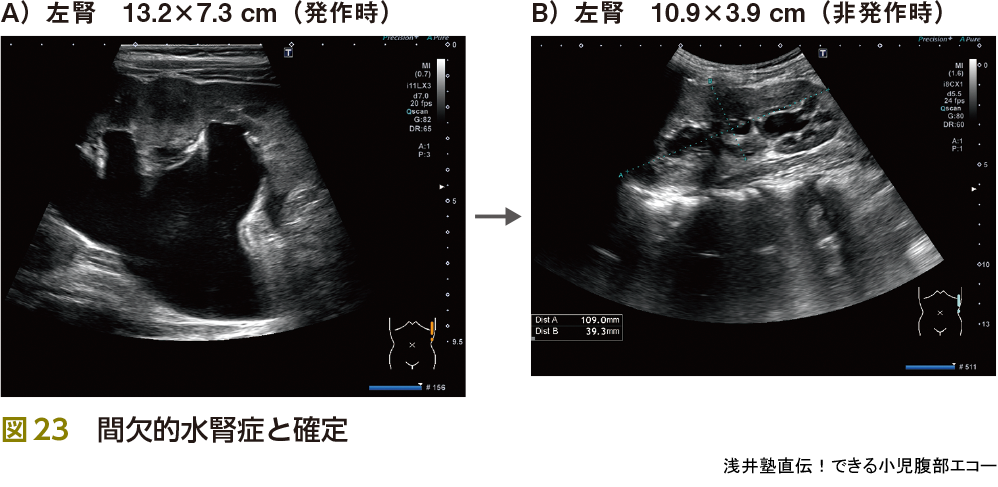

5)水腎症

水腎症は腎臓でつくられた尿の流れがせきとめられて,尿の通り道や腎臓の中に尿がたまって拡張した状態をいいます.腹痛の原因として重要です.特に腹痛の原因となるのはureteropelvic junction obstruction(UPJ:腎盂尿管移行部狭窄症狭窄)です(図22).そして原因不明のくり返す腹痛(同部位)では間欠的水腎症の発作を念頭に置く必要があります(図23).